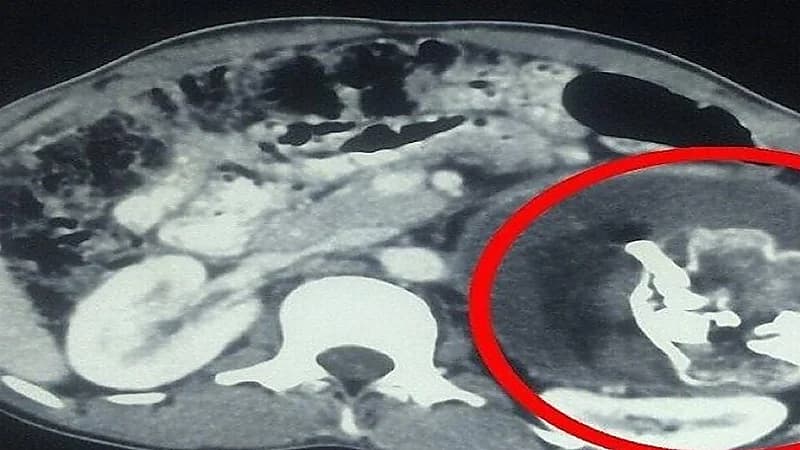

وكشف الفحص بالأشعة وجود تكوين في تجويف البطن يضم أنسجة رخوة، من الدهون والسوائل والبنية العظمية، وتمكن الأطباء من التعرف على عظام وجه متكونة، وعمود فقري، وأضلاع في الصورة.

ونجح الجراحون في إجراء العملية واستخراج الجنين الطفيلي غير المكتمل، الذي بلغ حجمه 8× 12 سنتيمترا.